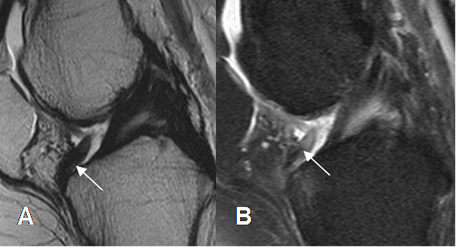

Fig 158. Plica infrapatelar.

A: RM sagital en T2 y B: RM sagital en STIR. Imagen paralela y por delante del LCA,

que corresponde a plica infrapatelar.